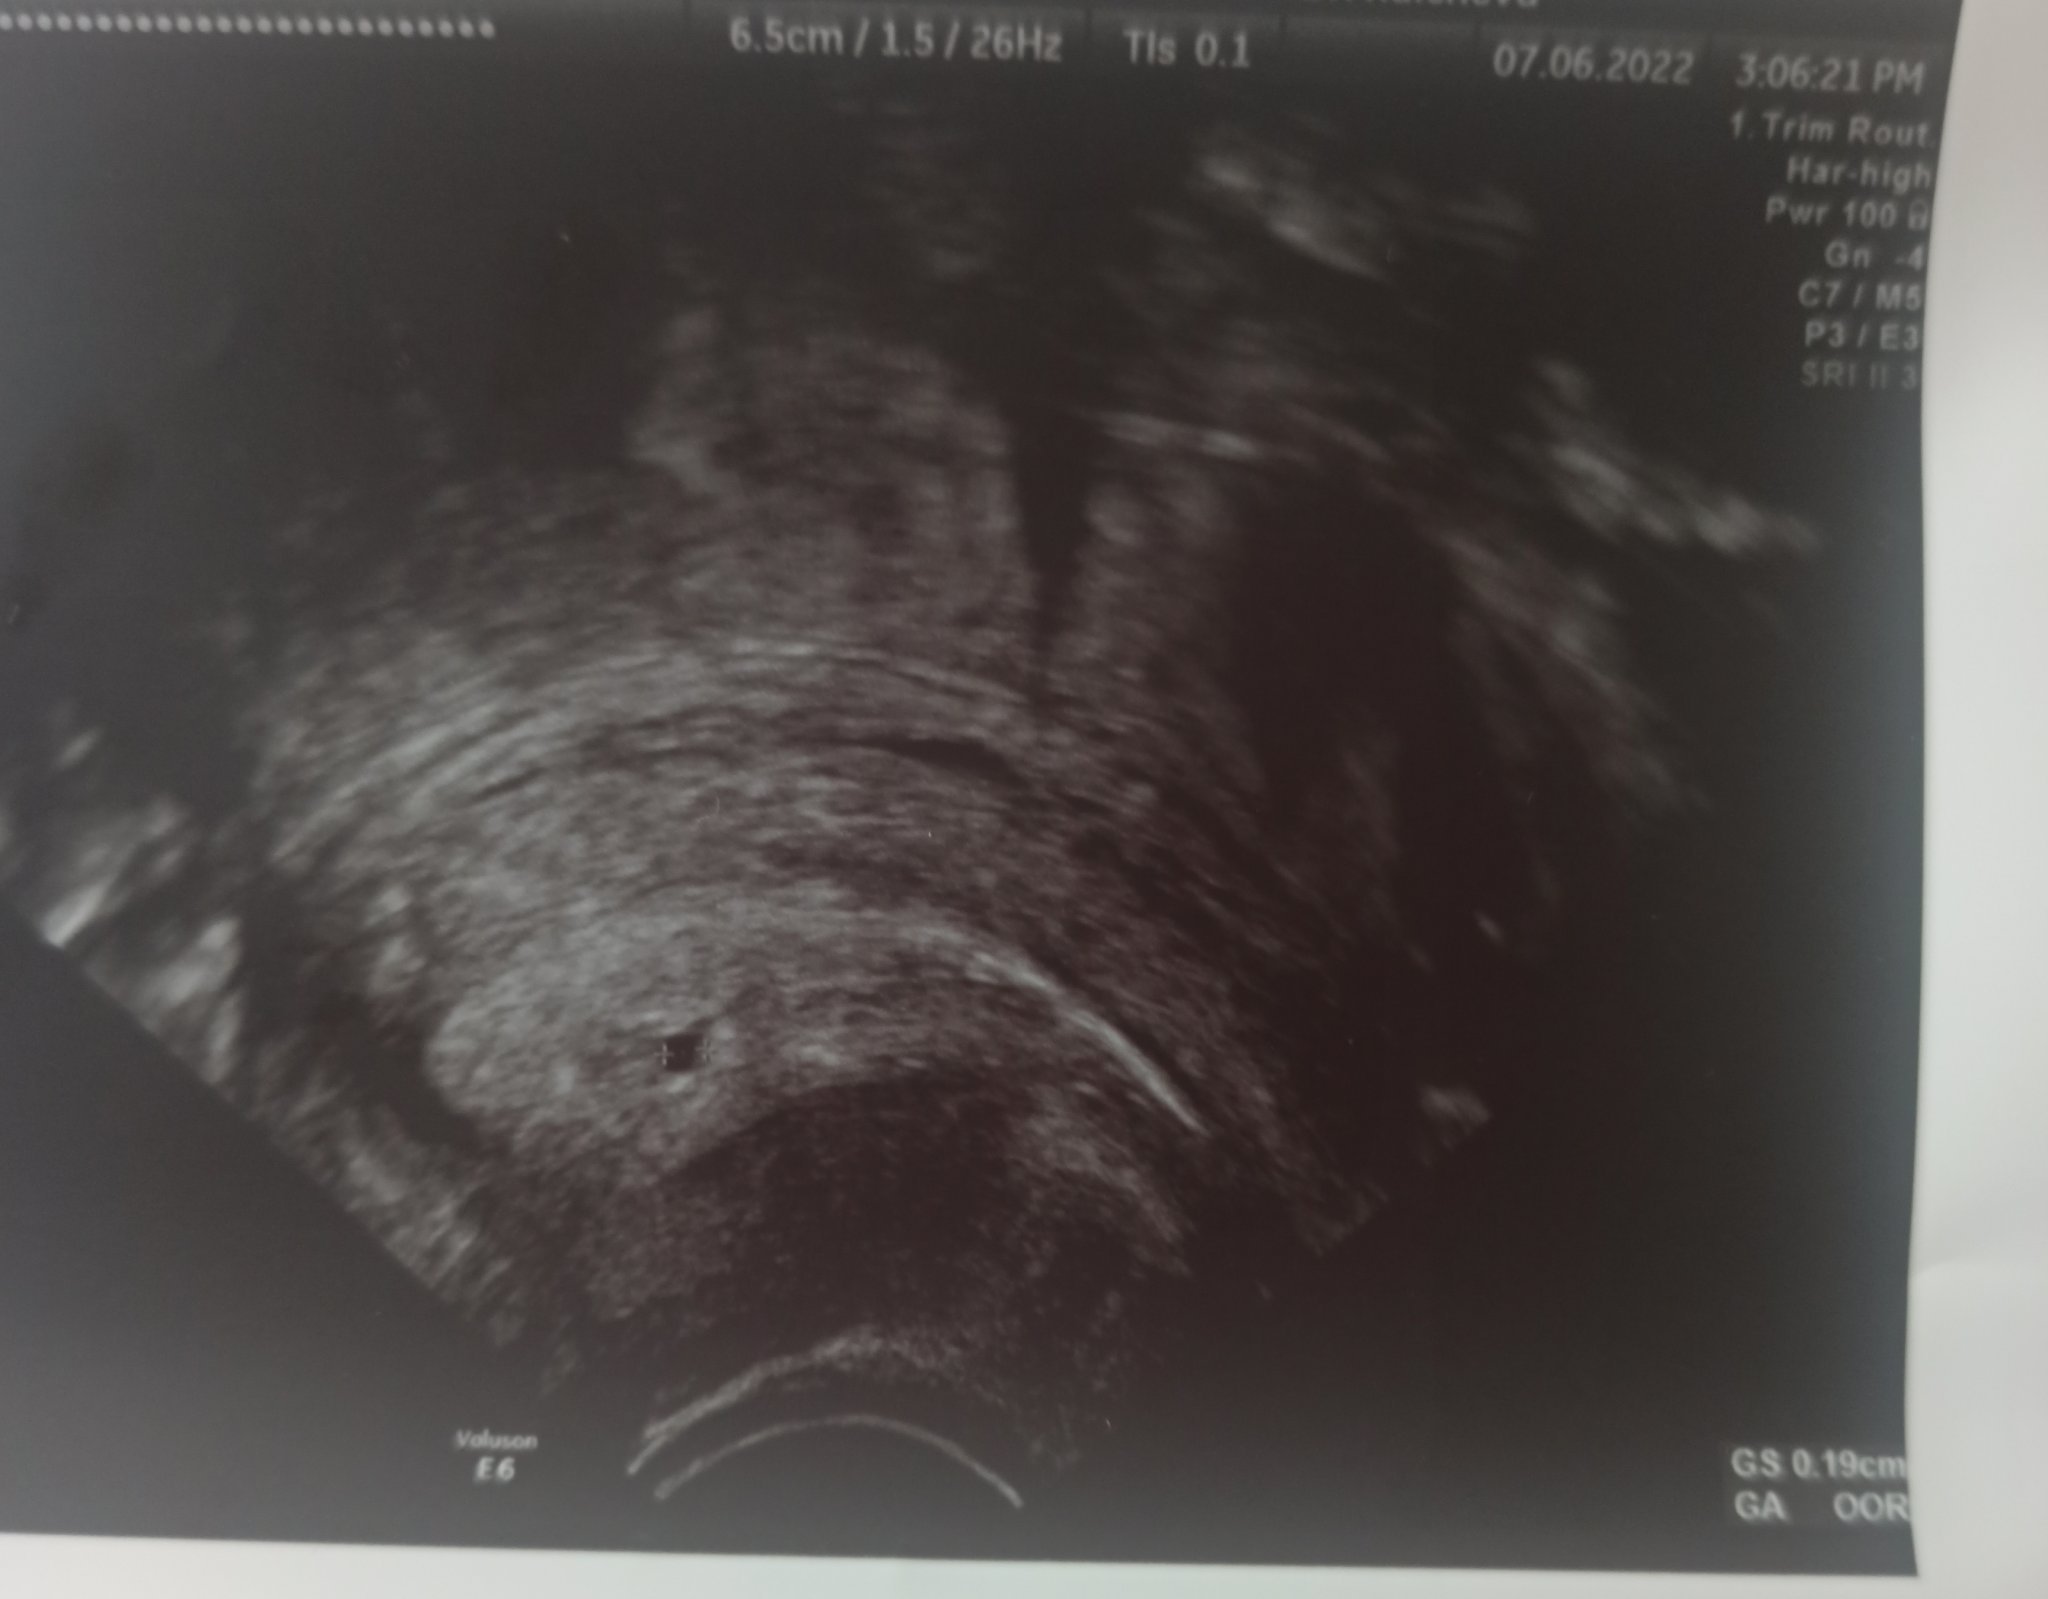

Момичета и аз се включвам след прегледа .Бях писала че съм с чхг което не се удвоява и съм имала една извънматочна бременност.При толкова ниска стойност от 480,която е от днес се видя една малка точка в матката също пише GS 0,19 см,незнам какво  точно значи.Отидох на възможно най-добрата апаратура,която намерих.В Четвъртък пак ще пускам бета Чхг и в петък на преглед .Казаха ми че най вероятно се отнася за празен сак,но като чуят че съм имала извънматочна добавят че може и псевдосак да е.Сега ако съм имала кървене и болки да бягам в спешното,ако не да си чакам до следващо чхг и преглед.От една страна се зарадвах,че този път се видя най после нещо в матката за първи път през живота ми,от друга се надявам ако е празен сак да се изчистя сама. Качвам снимка че аз не разбирам на такава малка стойност какво е това .